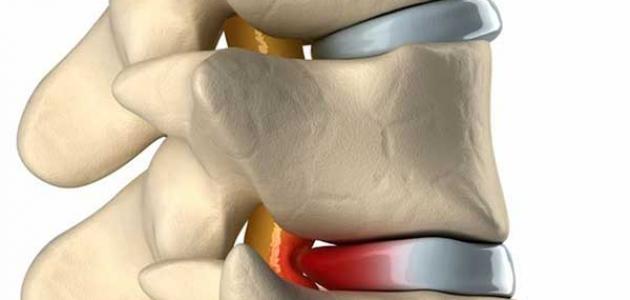

من المعروف أن العمود الفقري يتكون من عدة فقرات، فهو يتكون من سلسلة من الفقرات المكدسة على بعضها البعض، تمتد من أعلى الظهر إلى أسفله، وتشتمل عدة أجزاء منها 7 فقرات عنقية قريبة من العنق و12 فقرة صدرية قريبة من الصدر، و5 فقرات قطنية قريبة من البطن، والعجز والعصعص في القاعدة، وهي جميعها فقرات عرضة للانزلاق، ولدى كل منها آلامها وأسبابها وأعراضها. ولأنه تعدد أنواع الانزلاقات، فتعدد الأسباب والأعراض التي يمكن رصدها كالتالي:

الانزلاق الغضروفي القطني

يحدث هذا الانزلاق عند انزلاق الأقراص الموجودة بين عظام العمود الفقري في العنق حيث تحتوي هذه الأقراص على مادة هلامية لينة من الداخل وصلبة من الخارج، وقد يؤدي خروج هذه المادة الهلامية إلى حدوث انزلاق الغضروف في الفقرات العلوية حيث يشعر المريض بألم وخدلان في الأطراف العلوية مع الشعور بتنميل في الذراعين.

انزلاق غضروفي بين الفقرة الرابعة والخامسه

عندما يشعر المريض بألم في القدم يكون على امتداد العصب المصاب، فإنه قد يكون مصاب بالانزلاق في تلك الفقرات، والتي تعدد أسمائه فيشتهر باسم متلازمة القرص المنزلق أو الديسك أو الانزلاق الغضروفي أو ديسك الظهر.

ويحدث الانزلاق الغضروفي بين هذه الفقرات بسبب زيادة الضغط عليها نتيجة حمل مفاجئ أو مستمر، وعند انزلاقه من مكانه يسبب ضغط القرص على جذر العصب في هذا المكان.